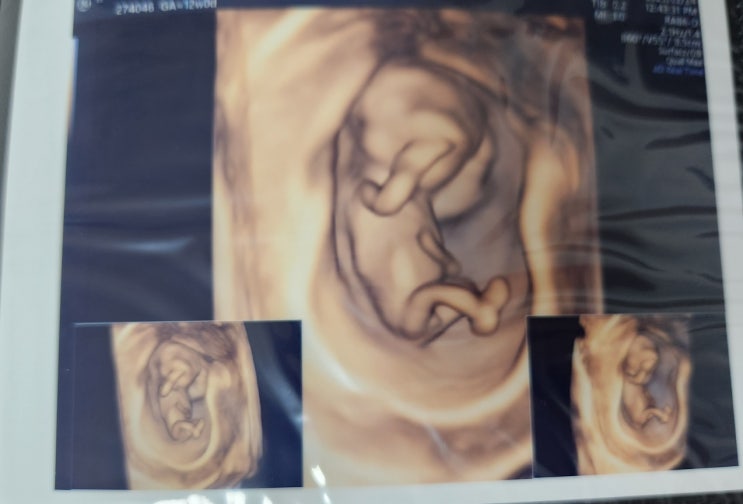

[ 임신기록 ] 임신10주 ~ 임신 16주 기형아검사2차까지

23.2.10 (임신10주차) 며칠전에 다른병원에서 진료를 봤지만, 기존에 예약한 날짜에 맞춰 병원을 방문. 이...

[ 임신기록 ] 임신 ~ 임신9주차 기록

12월달 해외다녀오고 일도 있어서 스트레스를 받아서 몸발란스가 깨졌다고 생각했지만, 홍냥예정일이 지나...